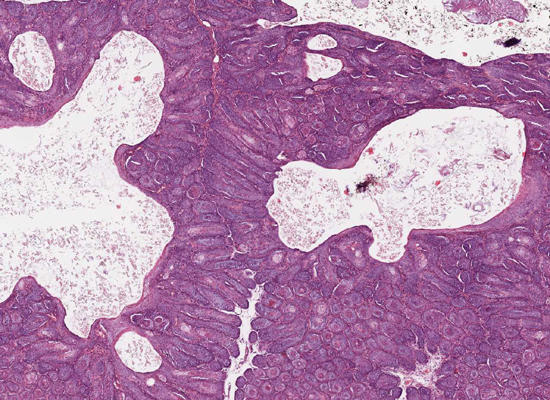

Darm: Protein-Losing-Enteropathy bei einem Hund

Dünndarmbiopsie, Hund, Bearded Collie, männlich, 13 Jahre;

Protein Losing Enteropathy: Hochgradige, chronische, pyogranulomatöse und nekrotisierende Entzündung mit Assoziation der "Lipogranulome" zu dilatierten Lymphgefäßen;